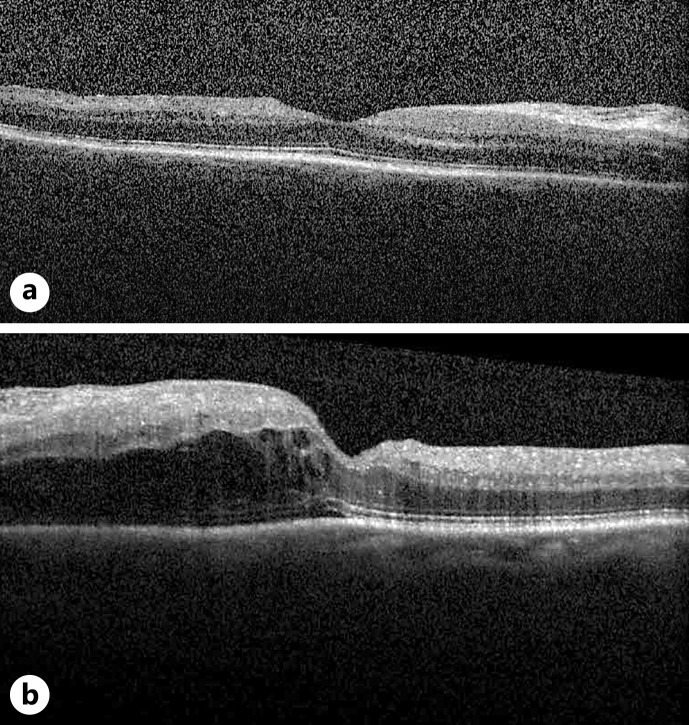

这是一份观察性病例报告,详细介绍了一例新确诊的系统性硬化症患者以双侧渗出性视网膜脱离为表现的硬皮病肾危象。一名 58 岁的女性患者原本身体健康,主要以视力不适为主要症状,经散瞳眼底检查和黄斑 OCT 扫描发现其患有恶性高血压(230/120 mm Hg)和双侧渗出性视网膜脱离。进一步的病史显示她有硬结、轻度吞咽困难和呼吸困难。根据最初的医学检查结果,她被诊断为弥漫性系统性硬化症和斯约格伦综合征,并发硬皮病肾危象。她被送入重症监护室,接受静脉降压治疗,以控制难治性高血压。治疗三个月后,她的视力症状和眼部检查结果均已缓解。由于存在渗出性视网膜脱离和其他高血压视网膜病变的迹象,需要对恶性高血压的潜在病因(包括系统性硬化症)进行彻底的系统筛查。通过紧急降压疗法治疗潜在疾病,解决了渗出性视网膜脱离问题,并恢复了硬皮病肾危象患者的视力。

This is an observational case report to detail a novel case of scleroderma renal crisis presenting as bilateral exudative retinal detachments in a patient with newly diagnosed systemic sclerosis. An otherwise healthy 58-year-old female presented primarily with vision complaints and was found to have malignant hypertension (230/120 mm Hg) and bilateral exudative retinal detachment on dilated fundus examination and macular OCT scan. Further history revealed sclerodactyly, mild dysphagia, and dyspnea. She was diagnosed with diffuse systemic sclerosis and Sjogren's syndrome complicated by an episode of scleroderma renal crisis based on initial medical workup. She was admitted to intensive care for management of refractory hypertension with IV antihypertensive therapy. Three months after treatment, her visual symptoms and ocular findings resolved. The presence of exudative retinal detachment among other signs of hypertensive retinopathy warrants thorough systemic screening for underlying causes of malignant hypertension, including systemic sclerosis. Treatment of the underlying disease with urgent antihypertensive therapy resolved the exudative retinal detachments and restored vision in the case of a scleroderma renal crisis.